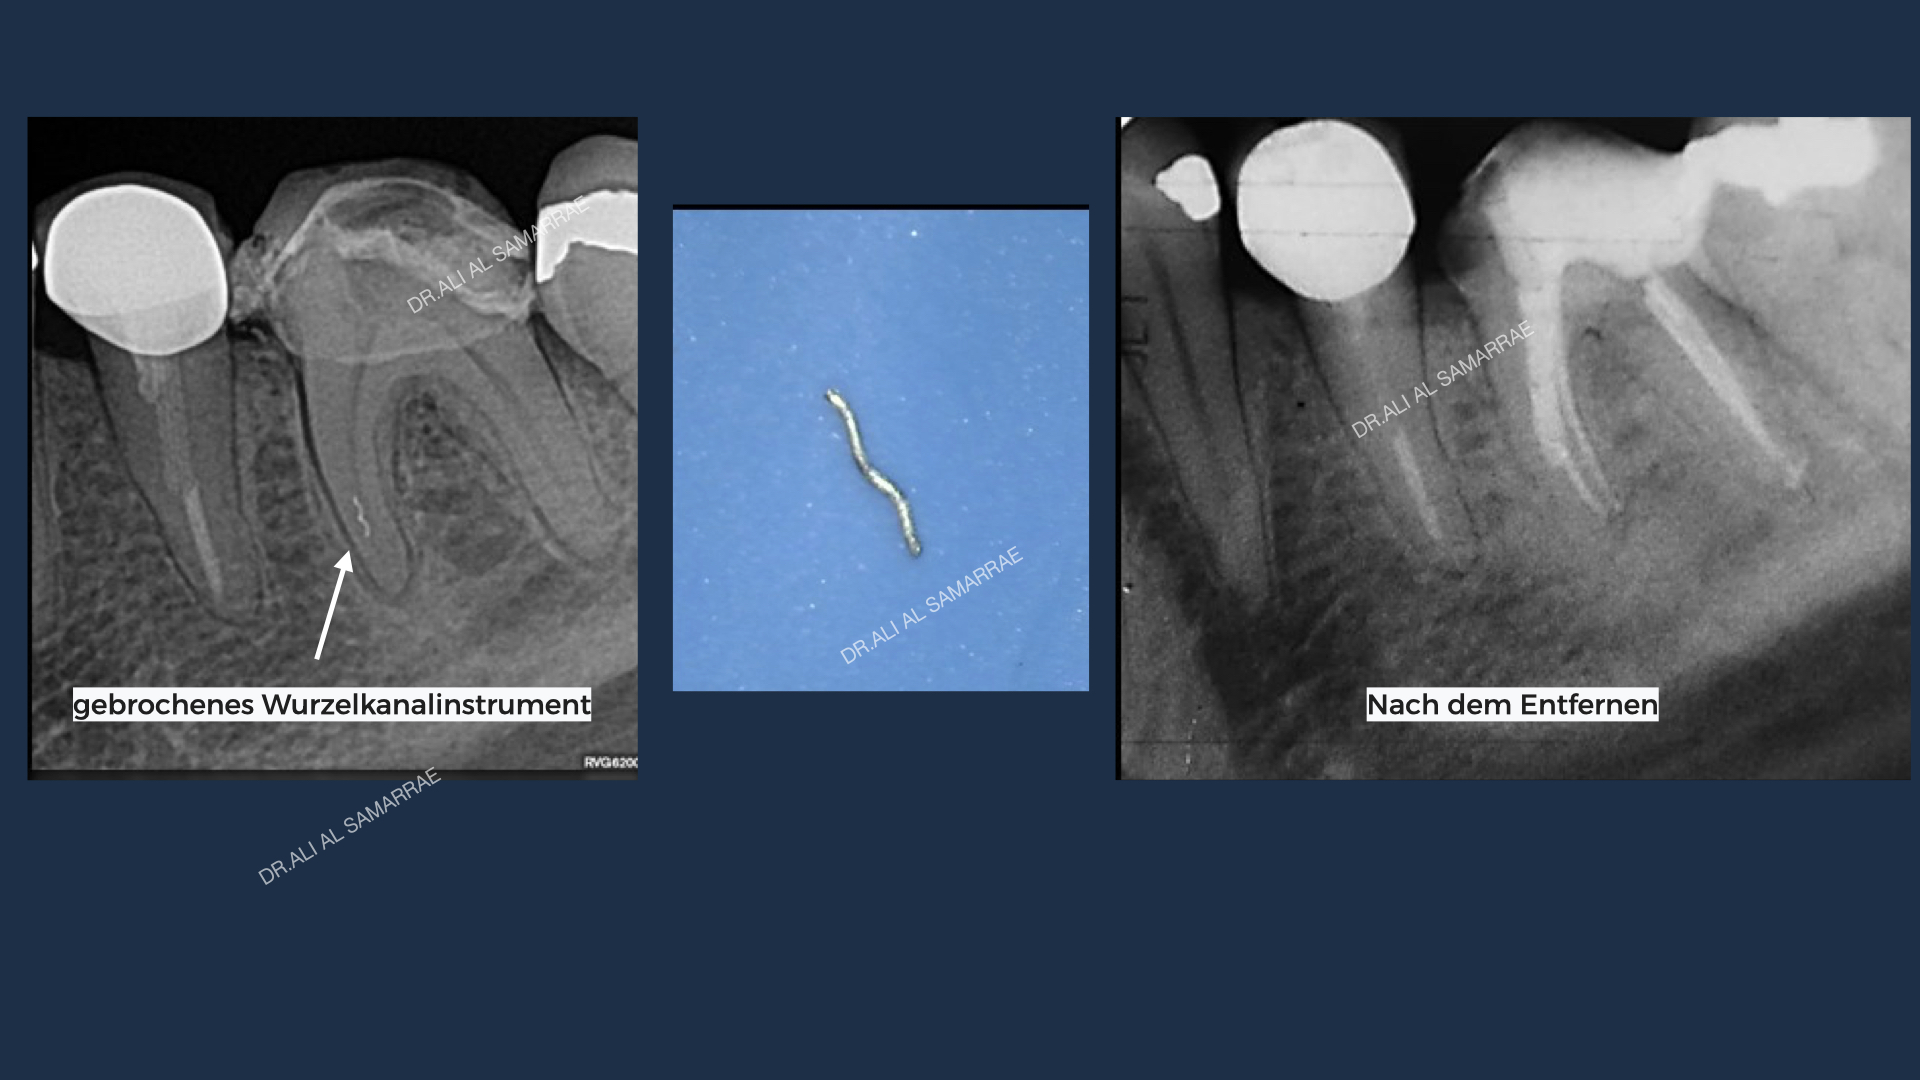

- Der Endodontist bzw. Mikroskopzahnarzt untersucht den Zahn und erstellt Röntgen. Unter Anästhesie, wenn gewünscht, wird dann gearbeitet. Wenn möglich wird ein sogenannter „Kofferdam“ über den Behandlungsbereich gelegt, um den Zahn zu isolieren und ihn während des Eingriffs sauber und speichelfrei zu halten.

- Als nächstes wird die Zahnkrone eröffnet und die sehr kleinen Wurzelkanäle gesucht.

- Nachdem die Wurzelkanäle gereinigt und ausgeformt wurden, füllt der Zahnarzt die Wurzelkanäle mit einem biokompatiblen Zement und einem gummiartigen Material, das als Guttapercha bezeichnet wird. In den meisten Fällen wird eine temporäre Füllung angefertigt.